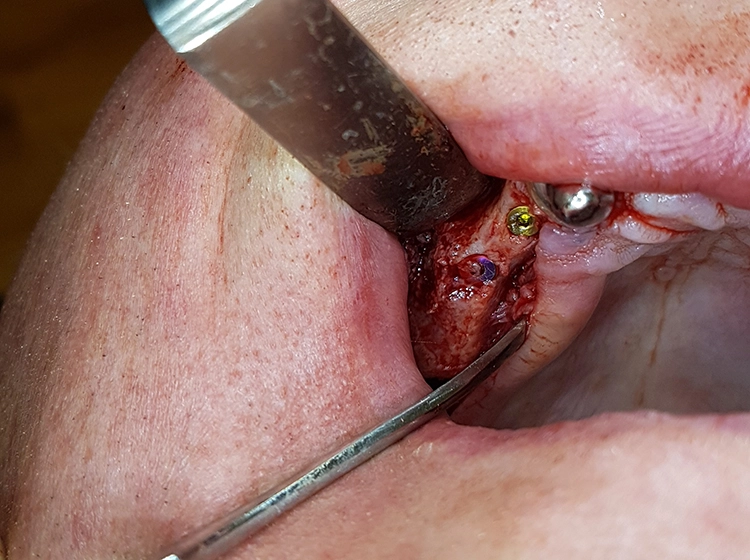

Mit einem Mukoperiostlappen wurden die lateralen Kieferhöhlenwände dargestellt und mittels Piezosurgery beidseitig laterale Fenster präpariert. Der piezochirurgisch abgelöste Knochendeckel ist eine patientenschonende Methode mit vorhersagbarem Ergebnis [4,7].

Bei der Elevation zeigte sich in regio 25 bis 27 eine Mund-Antrum-Verbindung (MAV), verursacht durch den parodontalen Knochenabbau. Da keine Anzeichen für eine Sinusitis vorlagen, wurde die MAV vor dem Verfüllen mit einer resorbierbaren, bovinen Kollagenmembran (Mem-Lok, BioHorizons Camlog) zur Kieferhöhle hin abgedeckt.

Apikal fixiert wurde die Membran durch das Verfüllen des Situs mit autologen Knochenspänen, retromolar aus regio 18 und 28 sowie 38 und 48 entnommen. Diese wurden jeweils zur Hälfte mit allogenem Knochenersatzmaterial (maxgraft, botiss biomaterials, Berlin) gemischt, womit eine natürliche Biofunktionalisierung des Knochenersatzmaterials erreicht wird.

Die präparierten Knochendeckel wurden in einer Kochsalzlösung zwischengelagert, um ein Austrocknen des entnommenen Knochens zu vermeiden. Nach dem Verfüllen konnten die Knochendeckel wieder passgenau in die Fenster repositioniert und das Weichgewebe vernäht werden.